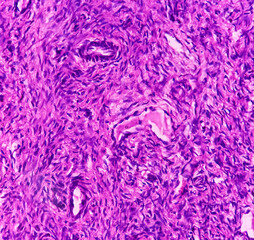

purple material..

purple material